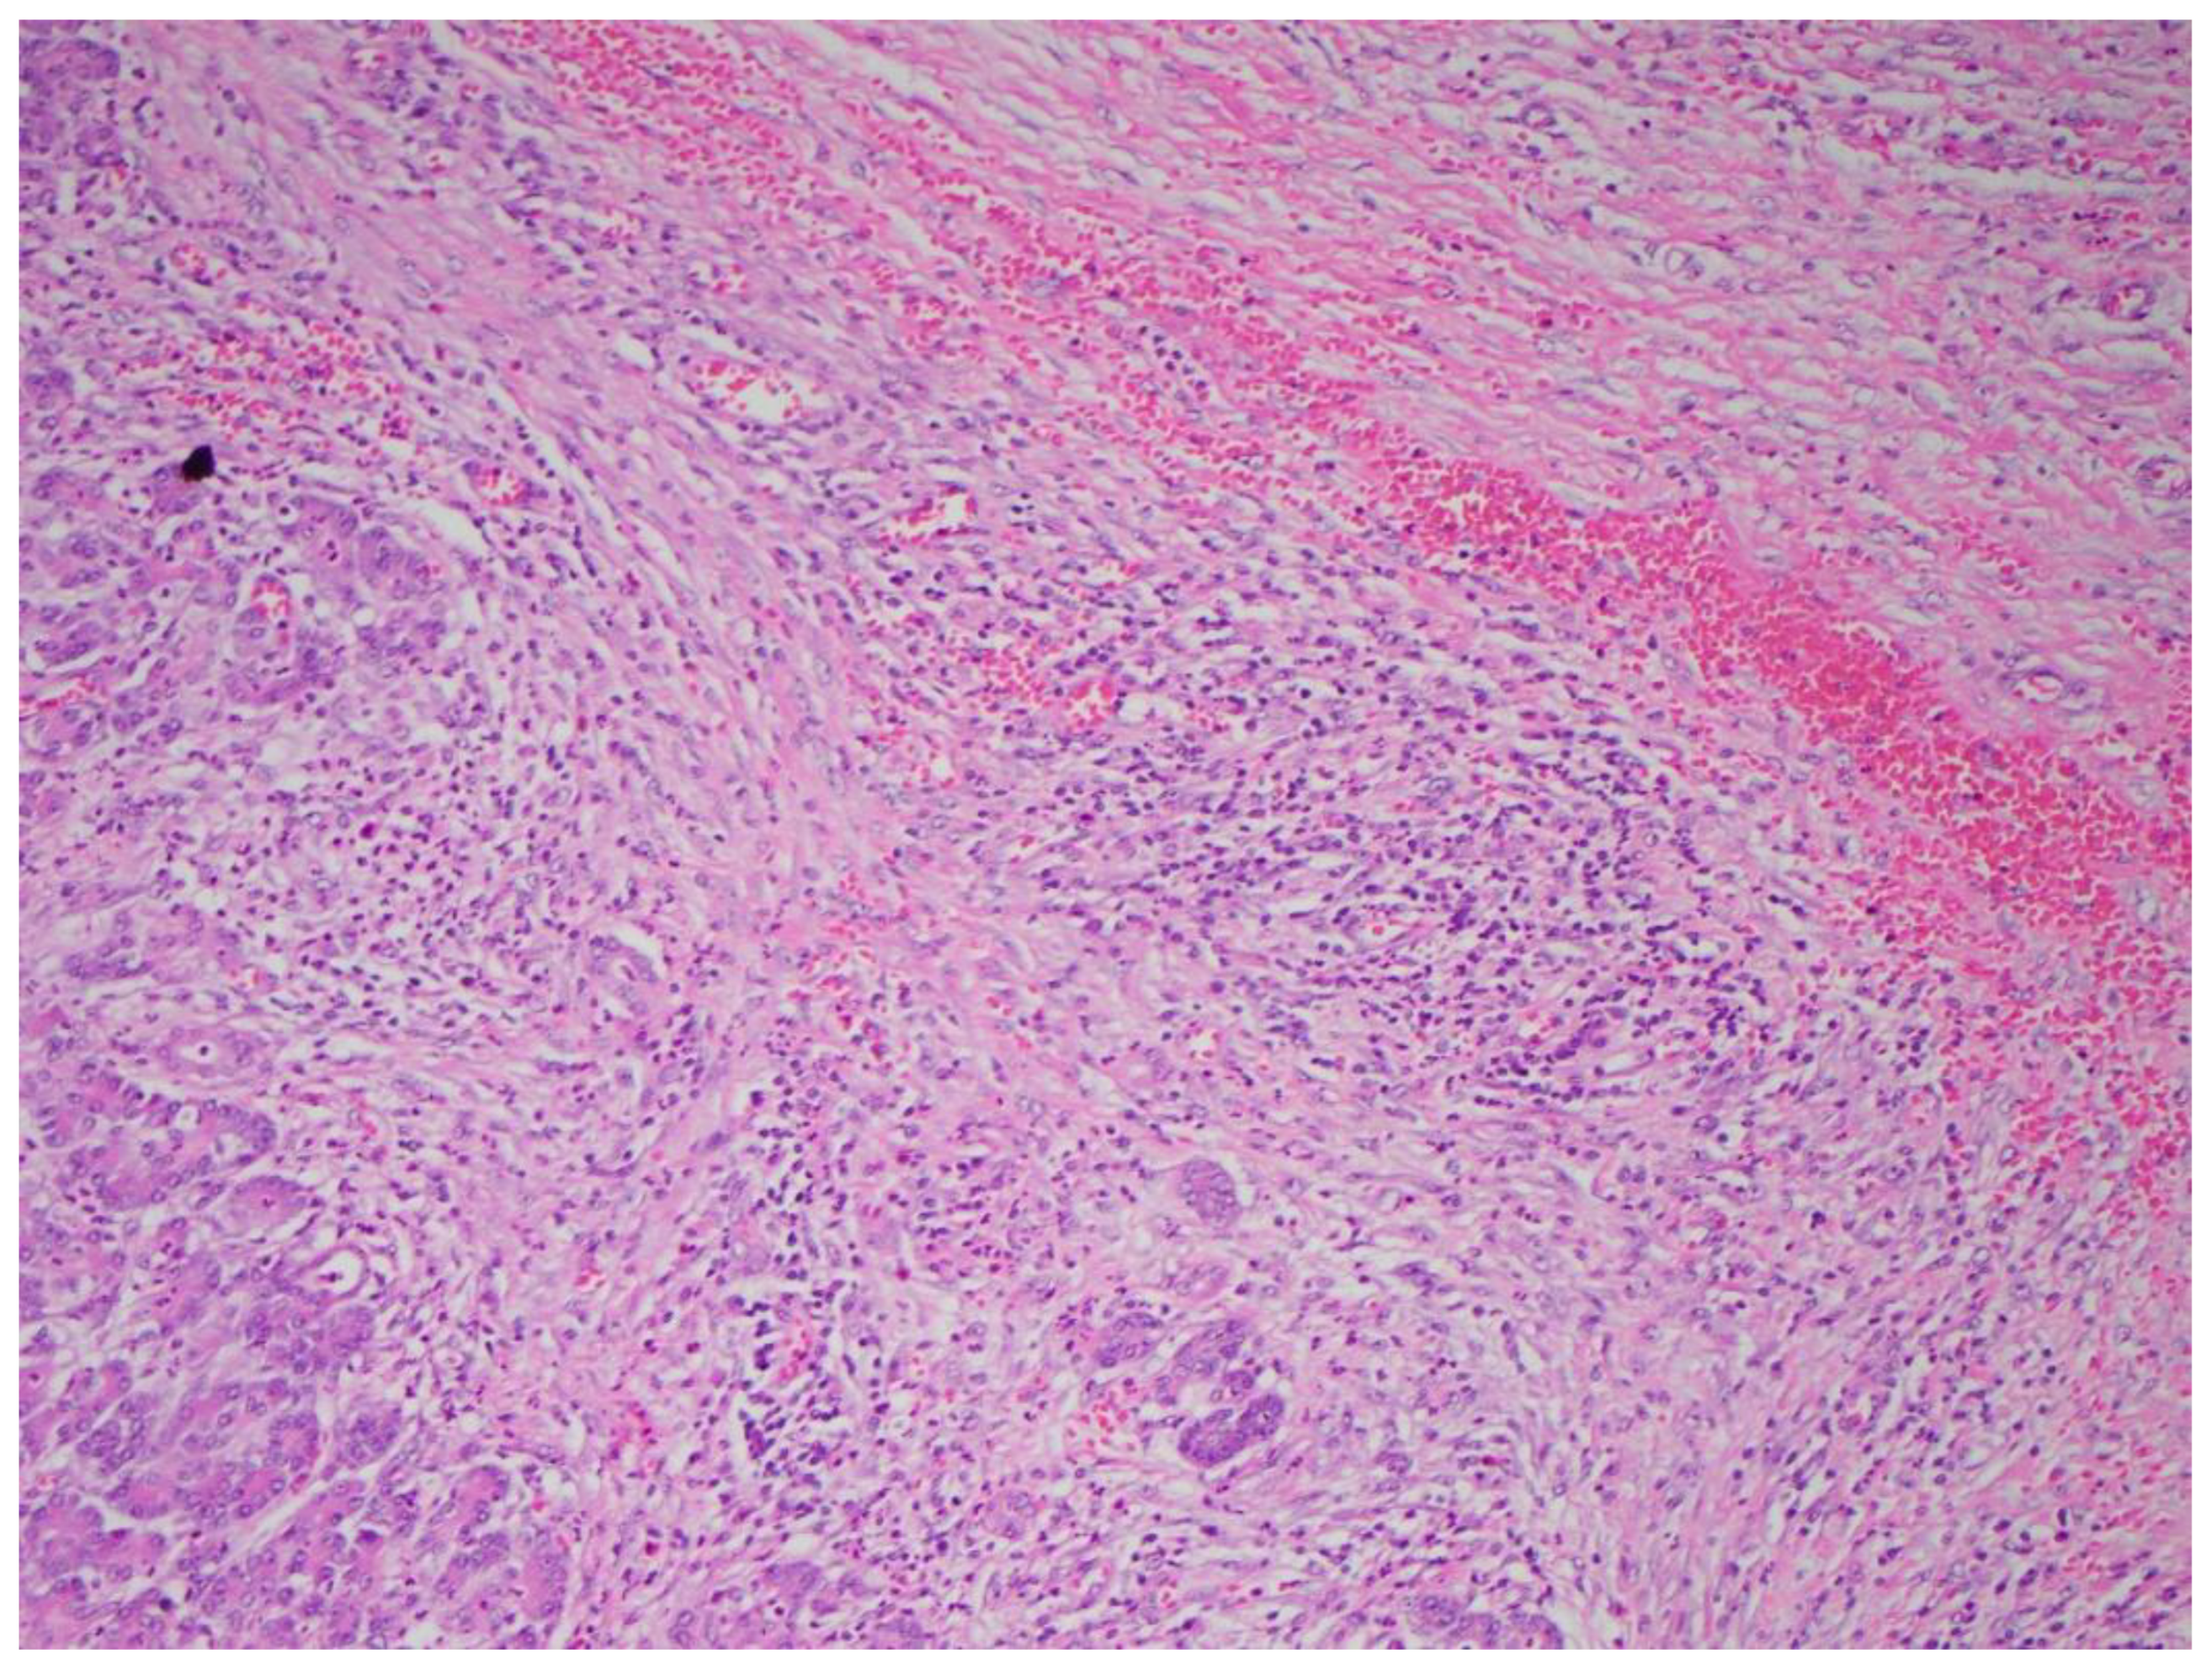

Multiple cytokines mediate a powerful pro-inflammatory immune response, such as tumor necrosis factor-alpha (TNF-a) and interleukins 1a, 1b, 6, and 18, exacerbating the initial pancreatic injury [37]. Pathologically, this appears as inflammation and can also be associated with a hemorrhage at the microscopic level (Figure 2 and Figure 3). The cytokine-mediated inflammatory cascade then extends the inflammatory cascade via lymphatic and systemic circulation into the liver, lungs, heart, kidneys, and gastrointestinal (GI) tract, leading to multi-organ injury [38]. This can cause systemic inflammatory response syndrome (SIRS), an early clinical feature that persists in cases of severe acute pancreatitis. Inflammation and damage to the GI tract can lead to bacterial translocation [39], and the species of bacteria involved are a predictive factor of disease severity, with Enterococcidae most frequently being associated with severe disease [40]. Obesity is also a predictive factor for moderate severity, and it leads to further deleterious effects through adipocyte lipolysis in the pancreas and adipose tissue [41,42] (Figure 2 and Figure 3).

Figure 2. Acute pancreatitis with hemorrhaging (H&E stain, 10×).